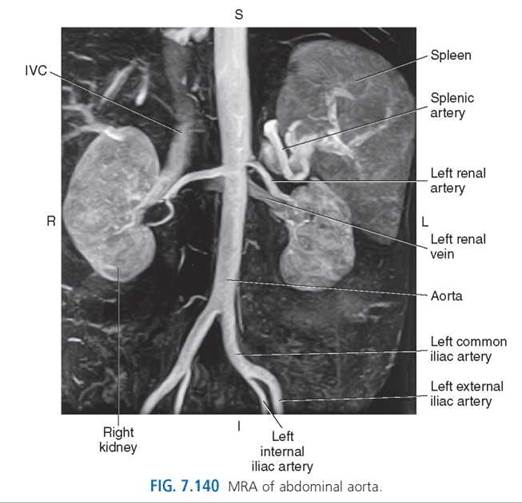

ABDOMINAL AORTA AND BRANCHES

The abdominal aorta is a retroperitoneal structure beginning, as an extension of the thoracic aorta, at the aortic hiatus of the diaphragm. The abdominal aorta gradually diminishes in diameter as it descends the abdomen just left of the midline next to the vertebral bodies. It delivers blood to all the abdominopelvic organs and structures. At approximately the level of L4, the abdominal aorta bifurcates into the right and left common iliac arteries. The branches of the abdominal aorta can be divided into the paired branches, including the inferior phrenic, lumbar, suprarenal, renal, and gonadal arteries; and unpaired branches, which include the celiac trunk, splenic, superior mesenteric, and inferior mesenteric arteries (Figs. 7.139-7.142). Each of these branches has a typical configuration that is described in this text; however, many normal variations of these vessels may occur.

Renal Arteries. The two large renal arteries arise from the lateral walls of the aorta just below the superior mesenteric artery. Each vessel travels horizontally to the hilum of the corresponding kidney (Figs. 7.1397.141 and 7.143-7.148). Because of the position of the aorta on the left side of the vertebral column, the right renal artery is slightly longer than the left renal artery.

The right renal artery passes posterior to the IVC and right renal vein on its course to the right kidney (Fig. 7.144). Typically, the left kidney is higher than the right kidney, which means the left renal artery is generally slightly superior to the right (Fig. 7.145). As each renal artery reaches the renal hilum, it typically divides into anterior and posterior branches and then into five segmental arteries—apical, upper, middle, lower, and posterior—(Figs. 7.146 and 7.148). Each segmental artery further divides into interlobar arteries, one for each pyramid and adjoining cortex. As the interlobar arteries curve over the renal pyramids, they become the arcuate arteries from which the interlobular arteries arise to supply the renal cortex (Fig. 7.146).